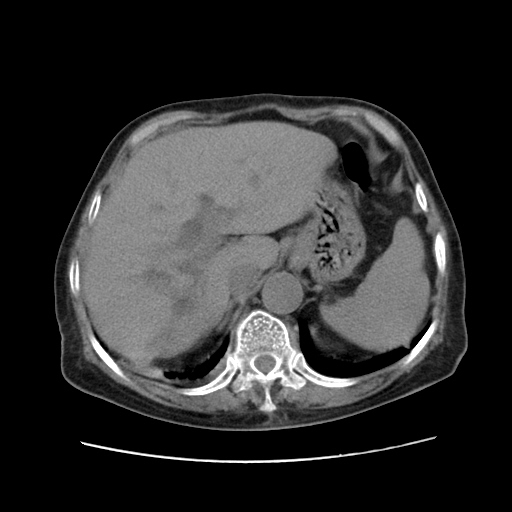

女,77.无不适

肝脏变异、异位胆囊,肝右叶肝内胆管结石并肝内胆管扩张。

肝右叶肝内胆管结石并肝内胆管扩张。

肝右叶肝内胆管结石并肝内胆管扩张

胆总管扩张

肝右叶肝内胆管结石并肝内胆管扩张。另:慢性胆囊炎!胆囊窝积液!

肝右叶肝内胆管结石并肝内胆管扩张。胆总管下段梗阻,考虑壶腹部占位。

右侧肝内胆管局限性扩张,其内密度不均匀,扩张的胆管壁增厚,考虑肝内胆管炎合并结石可能性大

肝右叶肝内胆管结石并肝内胆管扩张。胆总管下段梗阻,考虑壶腹部占位。支持